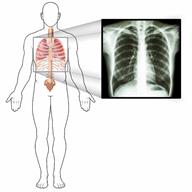

An outline of a person's body and an image of an X-ray of the person's chest.

Esse quadro clínico pode ser diagnosticado com base no seu histórico médico ou um exame físico. Você também poderá realizar exames, incluindo:

• Exames por imagem, como radiografia torácica ou ultrassom pulmonar.